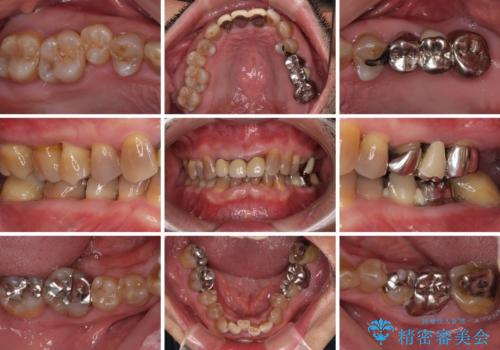

- 幼少期の薬剤の影響で歯が変色していていることを気にして来院された患者様です。

仕事も落ち着き、長年気にしていた前歯の色をきれいにしたいとのことでした。

上下ともに前歯のセラミッククラウンによる補綴治療を希望されていましたが、下顎前歯は叢生が強いため、補綴治療前に部分矯正を行って歯列を整えた上で、補綴治療を行うこととしました。

臼歯部には歯周ポケットのある箇所が散見されましたが、まずは前歯を治療したいとのことで、治療を進めました。

ディープバイトにより臼歯部に負担のかかる咬合であったので、補綴治療後には、矯正治療の後戻り防止もかねて、睡眠時にマウスピースを装着するように指示しました。